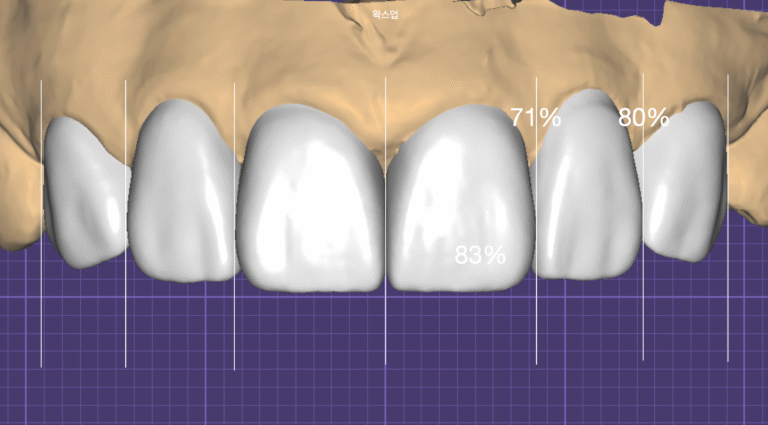

라미네이트 셰이드 매칭(Laminate Shade Matching): 자연스러움을 결정하는 네 가지 광학적 요소

2026년 05월 11일

서론: 라미네이트(Porcelain Laminate Veneer)의 심미적 성패는 형태와 정렬보다 색에서 갈리는 경우가 많습니다. 환자분이 “충분히 하얗게” 해 달라고 요청하셔도, 그대로 적용하면...